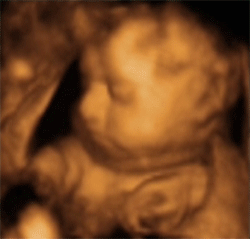

So sit back, relax, and enjoy Baby O in glorious 4D!

So far, so 3D... Time to add the 4th dimension!